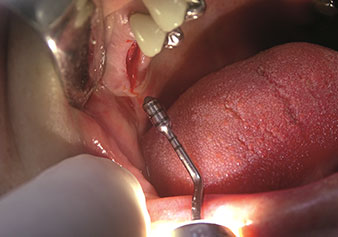

W&H bietet auch die perfekte Lösung für den internen Sinuslift an Nach der Kieferhöhlenpräparation mit dem

entsprechenden Instrumentarium (Abb. 3) erfolgt mit dem neuen Instrument Z35P (Abb. 4) die hydrodynamische Abhebung der Membran. Mit dem gleichen Instrumentenset kann auch die Implantatbett-Aufbereitung piezochirurgisch in aufsteigenden Durchmessern erfolgen (Abbildung drei und vier mit freundlicher Genehmigung von Dr. Mario Kirste, Frankfurt/Oder).

Präparation des Kieferhöhlenbodens und zum Anheben der Schneider'schen Membran mittels Kühlmedium (Instrument Z35P)

Abb. 4: Präparation des Kieferhöhlenbodens und zum Anheben der Schneider'schen Membran mittels Kühlmedium (Instrument Z35P). Foto: © Dr. Mario Kirste (Frankfurt / Oder)